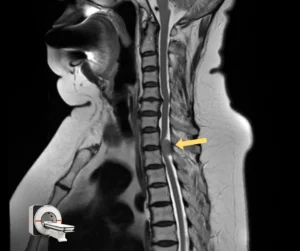

Проведённая МРТ грудного отдела позвоночника выявила две интрадуральные экстрамедуллярные опухоли, вызывающие критическую компрессию спинного мозга. Эти образования были диагностированы за 2–3 года до обращения. Однако, пациентка отказывалась от операции из-за страха, возраста и избыточного веса.

Учитывая возраст пациентки, общую соматическую нагрузку, прогрессирующую неврологическую симптоматику и необходимость срочно устранить компрессию спинного мозга, было принято решение о симультанном (одновременном) удалении обеих опухолей. Это решение позволило сократить время нахождения пациентки под наркозом и минимизировать риски. В таких случаях, когда дорога каждая минута, на помощь приходит спинальная хирургия с использованием современных технологий.

Операция была выполнена двумя командами нейрохирургов онкологов, работающих синхронно через разные хирургические доступы. Мы применили микрохирургическую технику, интраоперационный нейромониторинг и современное анестезиологическое обеспечение. Эти технологии позволили провести вмешательство максимально безопасно, сократить его длительность и уменьшить общую нагрузку на организм пациентки.